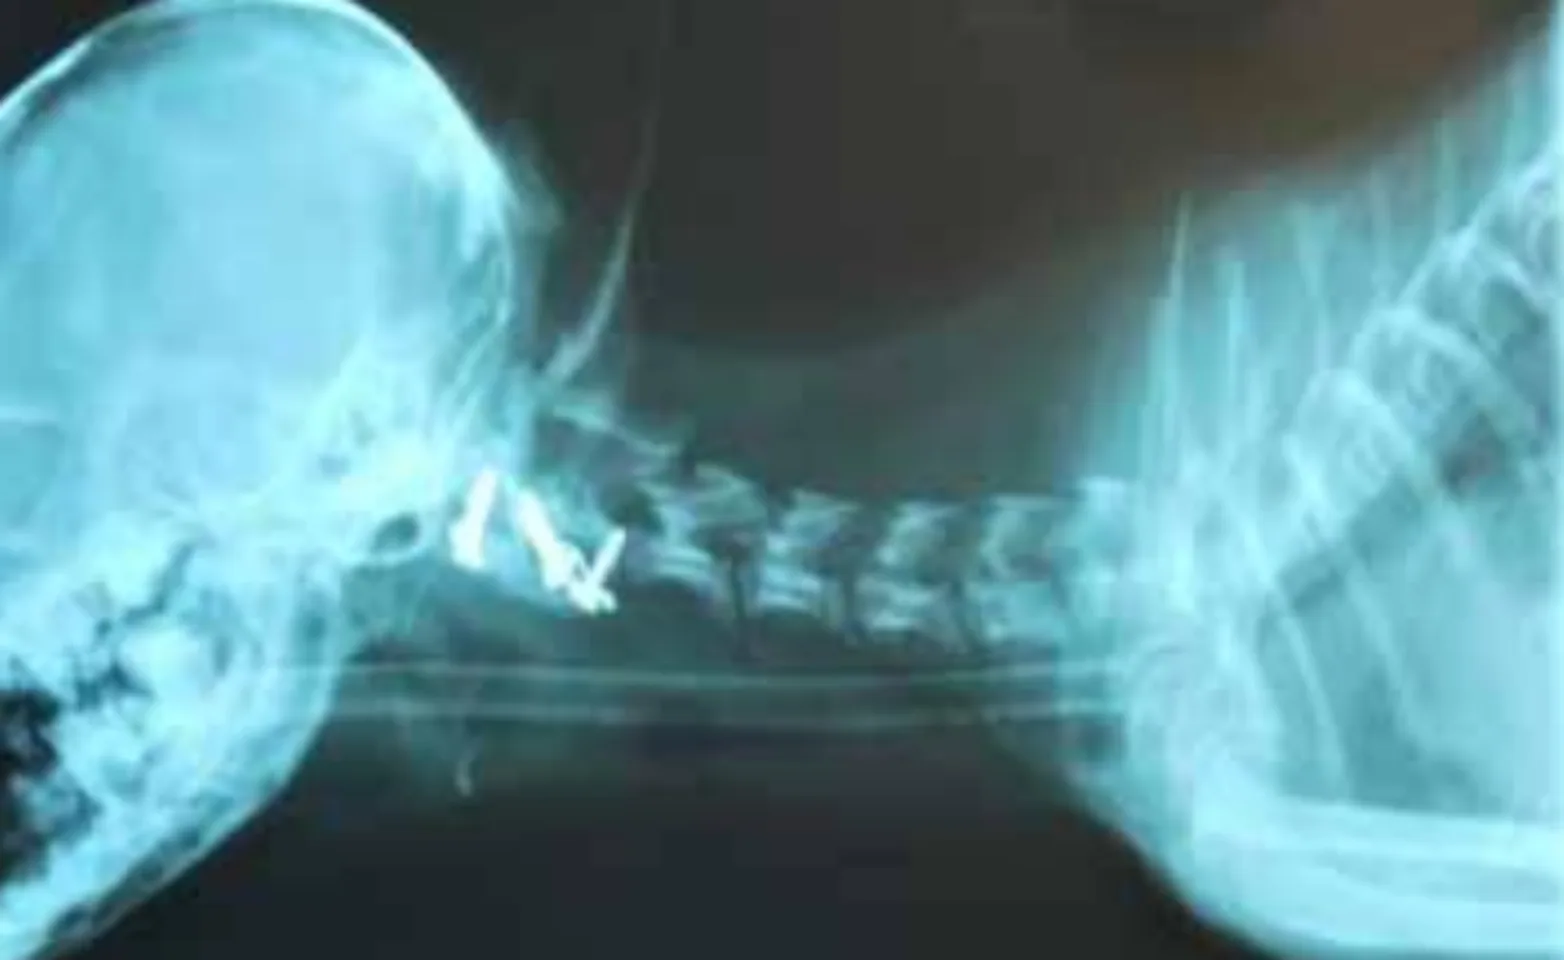

Either a dorsal, ventral, or combined dorsal and ventral technique can be used to stabilize the vertebrae. Dorsal stabilization is achieved by placing a non-absorbable monofilament suture between the dorsal lamina of C1-C2. The monofilament suture can pull through the thin bone, resulting in recurrence of instability and neurological dysfunction. Ventral stabilization involves removing the articular cartilage of the C1-2 articulation and placing a cancellous bone graft into the joint space. Small threaded pins or screws are placed using bone cement over the heads of the pins/screws to further augment the fusion. Eventually, the C1-2 articulation is fused with the ventral technique, resulting in a mechanically superior outcome. If substantial displacement of the C1 and C2 vertebral bodies is present, the dorsal procedure is initially done to realign the vertebrae, followed by a ventral fusion.

Overall, the prognosis for A-A instability is favorable, though the prognosis is guarded with more severe neurologic dysfunction. The dorsal technique is safer and technically easier to perform but also has a higher failure rate. The DVSC recommends performing a ventral fusion for a more permanent repair. We generally use fluoroscopy for the safe placement of pins and screws across the C1-2 articulation.